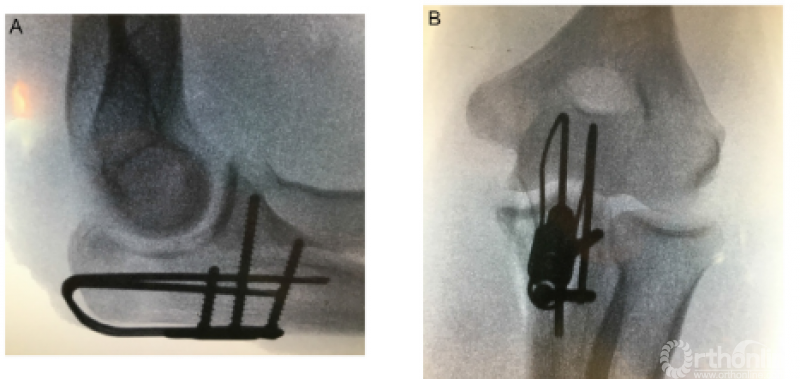

1、Lovy等采用鹰嘴雪橇板治疗Mayo II型鹰嘴骨折,在至少12个月的随访中,22例患者获得了满意的临床功能,均未取出内固定,也未出现感染或内固定相关的并发症,仅1例患者出现HO以及尺神经症状,做了关节镜下清理和尺神经前移。